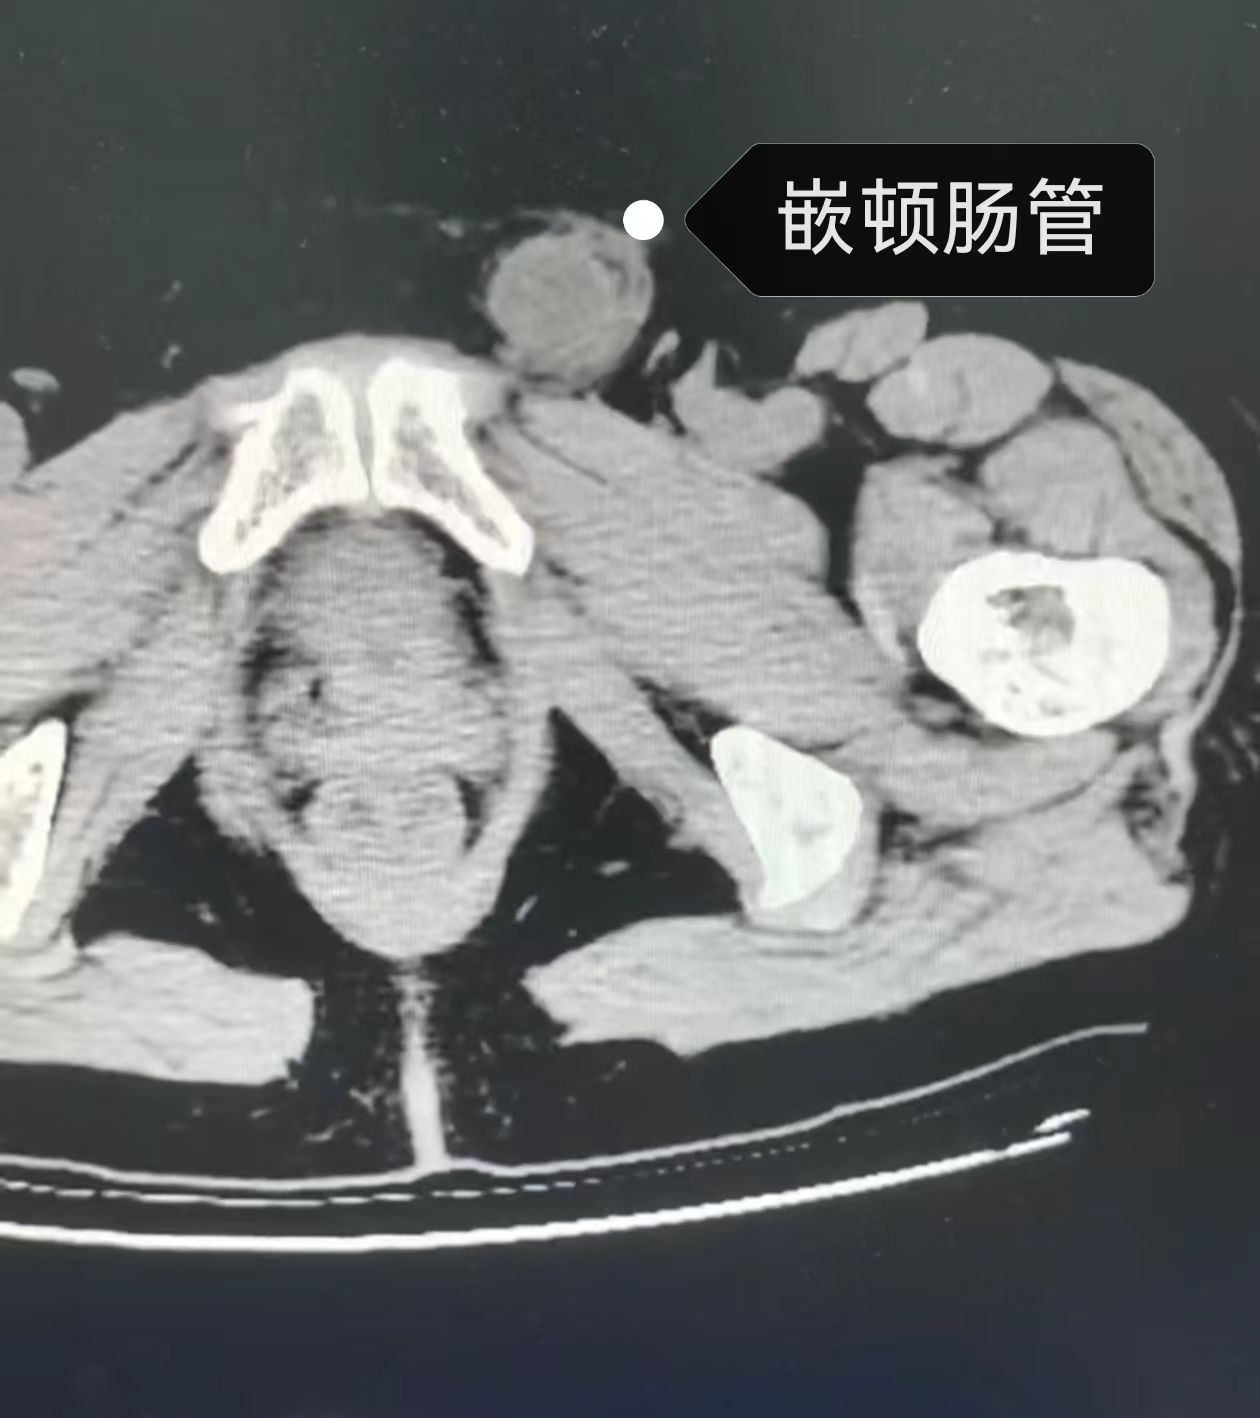

11月7日,一场惊心动魄的生命接力在我院普外科上演。普外科团队联合麻醉科、肾内科、ICU等多学科,成功为一名患有尿毒症的急性嵌顿疝患者实施了急诊腹腔镜手术,将患者从生命危险的边缘拉了回来。 患者为一名58岁女性,已有10余年的左侧腹股沟疝病史。两天前,她突然感到左侧腹股沟区疼痛难忍,原本可以回纳的肿物再也无法推回腹腔。家属紧急将其送至我院,经检查诊断为“左侧腹股沟嵌顿疝”,情况十分危急,嵌顿的肠管随时可能因缺血而坏死,引发致命的腹膜炎和感染性休克。 更棘手的是,该患者是一名长期透析的尿毒症患者,术前检查显示其肌酐高达935μmol/L,尿素18.21mmol/L,严重肾功能不全将会造成对麻醉和手术的耐受性极差,手术风险呈几何级数增长。 时间就是生命!面对这一复杂危重病例,普外科立即启动多学科诊疗(MDT)机制。普外科、麻醉科、肾内科及ICU的专家们迅速集结,共同进行术前评估,制定周密的救治方案。大家一致认为,必须先为患者进行急诊透析,改善内环境,为手术创造宝贵条件。在与肾内科的紧密协作下,患者被紧急送往透析中心。经过透析治疗,其肌酐水平成功回落至297μmol/L,手术窗口终于打开! 术前准备就绪,普外科团队为患者急诊施行“腹腔镜下经腹腹膜前疝修补术(TAPP)”。术中,腹腔镜探查发现部分肠管已嵌入疝囊,颜色发暗,血运不佳。普外科潘璇医生凭借娴熟的腔镜技术,在狭小的空间内精准、轻柔地操作,成功将嵌顿的肠管松解复位。经过温盐水湿敷后,肠管颜色逐渐恢复红润,血运良好,避免了肠切除的更大创伤。随后,医生们熟练地置入补片,完成了疝的无张力修补。整个手术过程争分夺秒,历时仅半小时余,一气呵成。 术后,在病房医护人员的精心照料下,患者恢复良好,各项生命体征平稳。这场与死神的赛跑,我们赢了! 此次成功救治,不仅体现了我院普外科在处理急腹症方面的高超技术和快速反应能力,更彰显了我院多学科协作(MDT)模式在处理复杂危重病例中的关键作用。从急诊透析到精准手术,再到术后监护,每一个环节都无缝衔接,共同为患者筑起了一道坚不可摧的生命防线。这既是对“以患者为中心”服务理念的深刻践行,也是我院综合救治实力的又一次有力证明。未来,我们将继续精进技术,深化协作,为更多急危重症患者带来生命的希望。